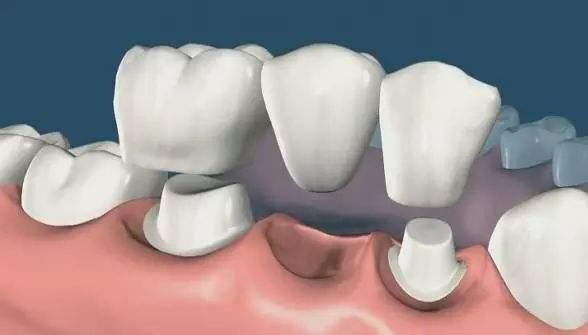

1、固定橋修復(fù)

適用于:1-2顆牙缺失或散在的多顆牙缺失,缺牙兩側(cè)還有健康的牙齒存在。

優(yōu)點:是能比較快的修復(fù)缺失的牙齒,拔牙后三個月就可以修復(fù),能很好的恢復(fù)牙齒的咀嚼功能,全瓷固定橋還有很好的美觀作用。

缺點:需要將兩側(cè)的健康牙齒磨小后當(dāng)基牙來修復(fù)中間缺失的牙齒。不僅增加了兩側(cè)牙齒的負(fù)擔(dān)(2顆牙承受3顆牙的咬合力),而且會出現(xiàn)一顆基牙出問題需拆除后重新修復(fù)的風(fēng)險。